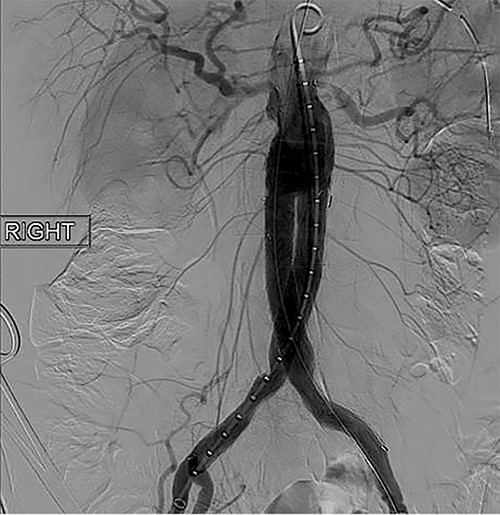

To obtain vascular access, bilateral cutdown technique was used to dissect the common femoral arteries. The femoral arteries were cannulated, the patient heparinized, and an arteriogram obtained (Fig. 2). The main body of the graft was deployed without complication, followed by bilateral iliac limb extensions. The graft was treated with the Molding & Occlusion Balloon (MOB) at all attachment points. Repeat arteriogram demonstrated excellent technical result without evidence of endoleak (Fig. 3). Protamine was administered for reversal of heparin, bilateral groin incisions were closed, and nasogastric tube (NGT) was left in place on low intermittent wall suction. Aspirin/Plavix therapy was continued.

Intraoperative fluoroscopy illustrating successful endovascular aneurysm repair (EVAR).